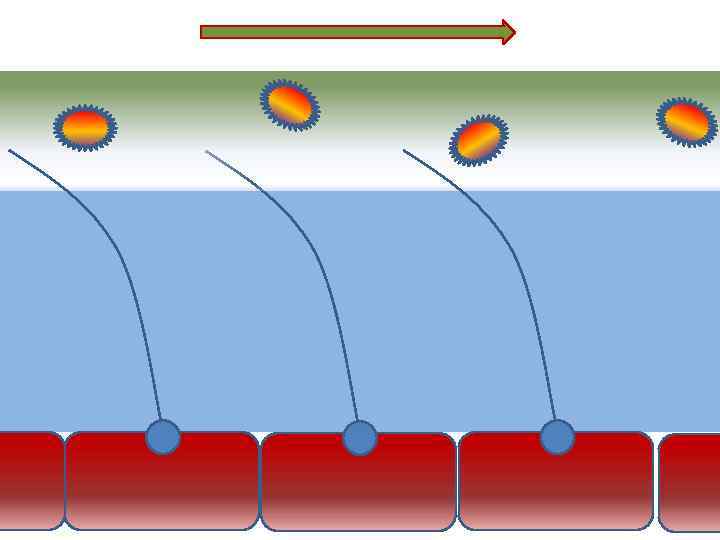

Факторы риска Недостаточное увлажнение дыхательной смеси • естественное удаление бактерий • состояние эпителия трахеи и бронхов

Факторы риска Недостаточное увлажнение дыхательной смеси • естественное удаление бактерий • состояние эпителия трахеи и бронхов

Движение клеток реснитчатого эпителия Движение вперед 1 – 3 Обратное движение 4 – 8

Движение клеток реснитчатого эпителия Движение вперед 1 – 3 Обратное движение 4 – 8

Механизм защиты легкого Слизь (зеленый цвет) нейтрализует и связывает патогенную флору(синий цвет) Слизь – это барьер между клетками и патогенной флорой Слизь – это транспортное средство

Механизм защиты легкого Слизь (зеленый цвет) нейтрализует и связывает патогенную флору(синий цвет) Слизь – это барьер между клетками и патогенной флорой Слизь – это транспортное средство